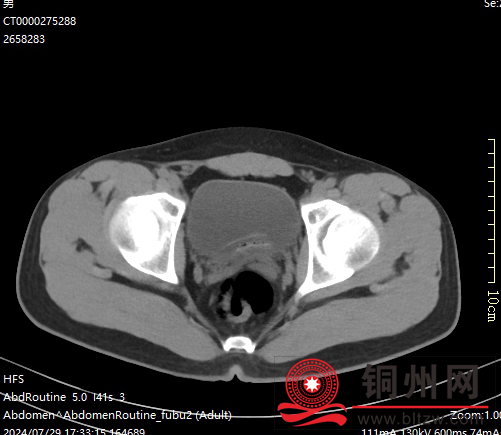

d4cf14bb50102cb1d0ca9ba3e128342e.png

上图:入院CT检查考虑膀胱异物(黄鳝)